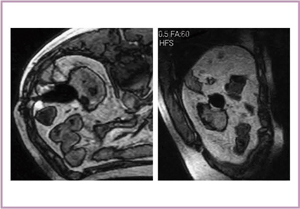

外側に発育するRCCに対し,多方向からMRIを撮像して,凍結状況と腫瘍の関係を確認しながら凍結治療を行った。2週間後の造影CTでは,辺縁部に淡い造影効果が見られ,内側はしっかりマージンが取れており,治療は成功したと評価した。しかし,10週後に造影CTを行ったところ,早期の造影効果と後期での抜けが認められ(図8),辺縁部に残存腫瘍があることが確認されたため,再度の凍結治療を行った(図9)。MRガイド下の経皮的凍結治療は比較的安全に行えるため,繰り返し施行することが可能である。本症例では,1年後の造影CTで造影効果は完全に消失し,腫瘍部位も収縮していた。

図8 症例2:66歳,男性,左腎癌 |

図9 症例2の再凍結治療中のMRI |